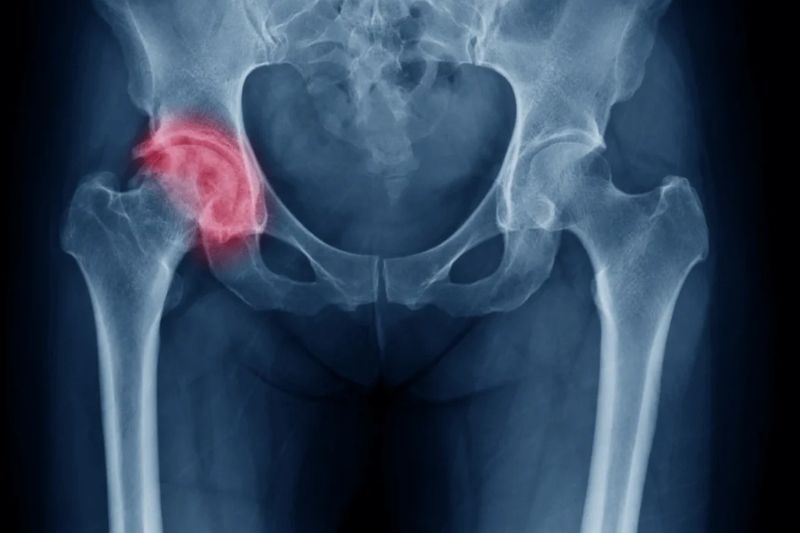

2.3. Chụp X-Quang chẩn đoán thoái hóa khớp háng

Chụp X-quang là một phương pháp chẩn đoán hình ảnh phổ biến và hiệu quả để xác nhận thoái hóa khớp háng. Hình ảnh X-quang cung cấp cái nhìn chi tiết về cấu trúc bên trong khớp, giúp bác sĩ nhìn thấy:

– Khoảng cách khớp bị hẹp: Khi sụn khớp bị mòn, không gian giữa các đầu xương sẽ bị hẹp lại.

– Gai xương: Các gai xương mới hình thành xung quanh khớp là dấu hiệu rõ ràng của thoái hóa.

– Cấu trúc xương: Bác sĩ có thể kiểm tra xem các xương trong khớp có thẳng hàng không và có mảnh sụn hoặc xương nhỏ nào bị bong ra gây cọ xát không.